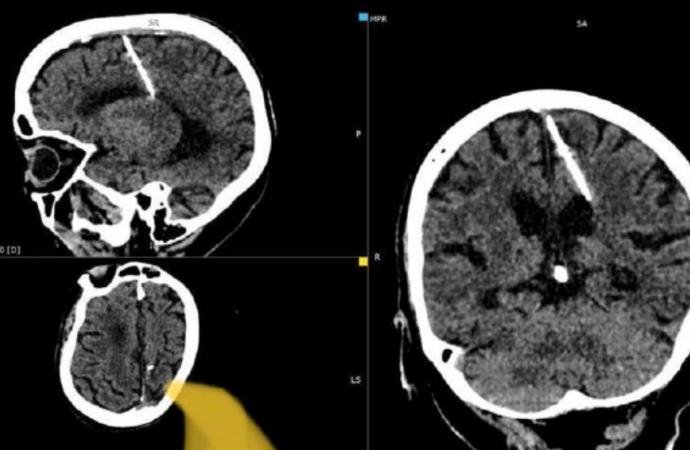

Bu tuhaf vaka, bu ayın başlarında Rusya’nın uzak doğu bölgesinin açıklarındaki uzak bir ada olan Sakhalin’deki yerel sağlık yetkilileri tarafından bildirildi. Doktorlar, bu iğne ile ilgisi olmayan bir CT taraması sırasında kadının beyninde 3 santimetrelik iğneyi keşfettiği bildirildi. İğnenin görüntüleri sağlık bakanlığının Telegram sayfasında paylaşıldı.

Sağlık bakanlığının belirttiğine göre iğne muhtemelen 1943’teki doğumundan hemen sonra kızın ebeveynleri tarafından batırılmıştı. Trajik bir şekilde, 2. Dünya Savaşı’ndan etkilenen bölgelerde yiyecek kıtlığıyla karşı karşıya kalan aileler, bazen özellikle bu yöntemi kullanarak bebeklerini öldürmeyi seçiyordu. İğne beynin fontaneline (bebeğin başındaki yumuşak nokta – bıngıldak) batırılıyordu ve bu delik daha sonra hızla kapanarak eyleme dair her türlü kanıtı ortadan kaldırıyordu. Yerel sağlık departmanı yaptığı açıklamada, “Yıllar süren kıtlık sırasında bu tür vakalar nadir değildi” dedi.

Şaşırtıcı bir şekilde, parietal lobuna yerleştirilen iğneye rağmen kadın hayatta kaldı. Dahası, yaralanma sonucu ciddi sağlık sorunları yaşamamış, hatta baş ağrıları bile yaşamamış gibi görünüyor. Ve şu anda herhangi bir tehlikede olduğu düşünülmüyor. Sağlık bakanlığının açıklamasına göre, iğneyi çıkarmaya çalışmanın kadına gerçekten zarar verebileceği ihtimalini göz önüne alarak, ilgili doktor kadının durumunu izlemeye karar verdi.